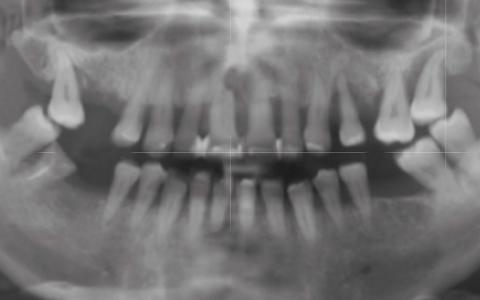

Paciente 50 años con grave problema periodontal. Severa pérdida de inserción y movilidad dental además de problema estético. Desea mejorar su sonrisa.

Plan de tratamiento: Rehabilitación maxilar con colocación de 10 implantes Microdent de conexión protésica interna del sistema Genius con cirugía guiada.